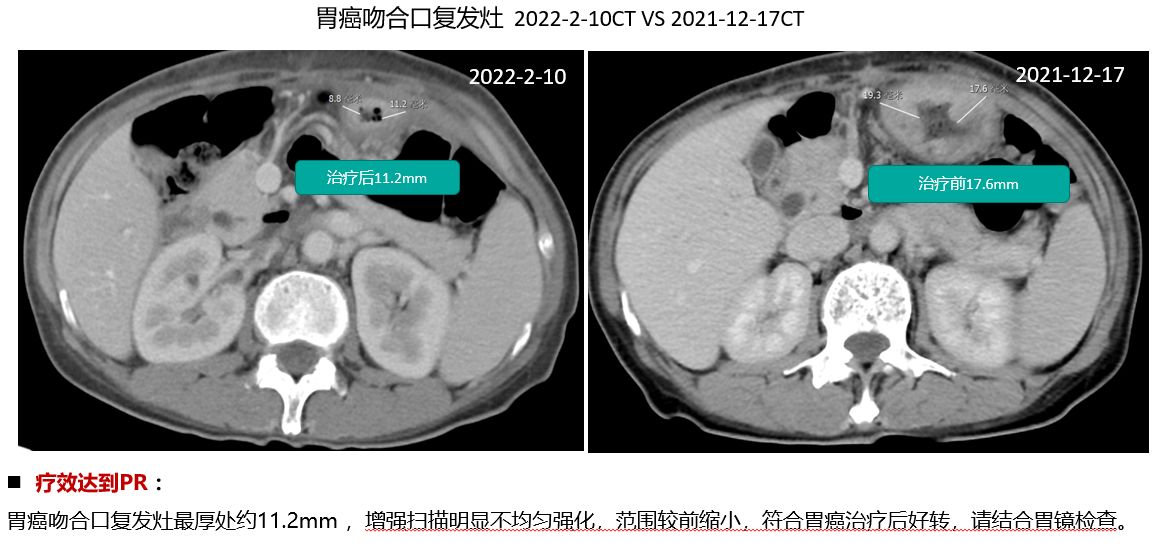

晚期胃癌患者免疫联合化疗案例

1. 治疗2月后CT评估显示肝转移病灶从18cm缩小至7cm

2. 腹水显著减少;患者体感、生活质量显著改善